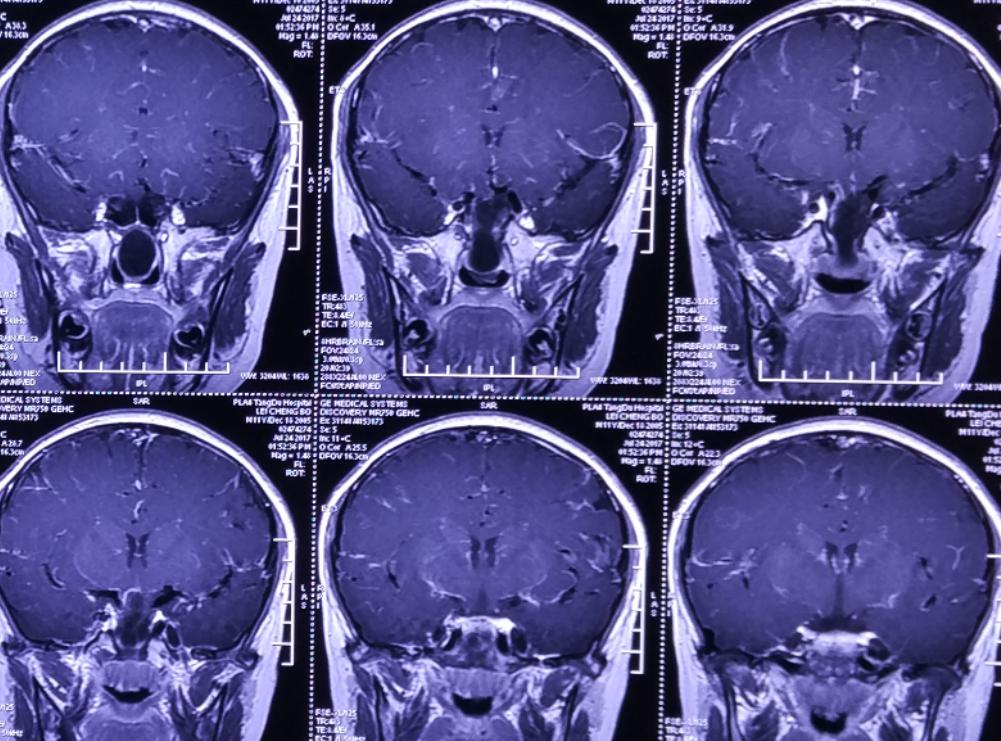

术后影像